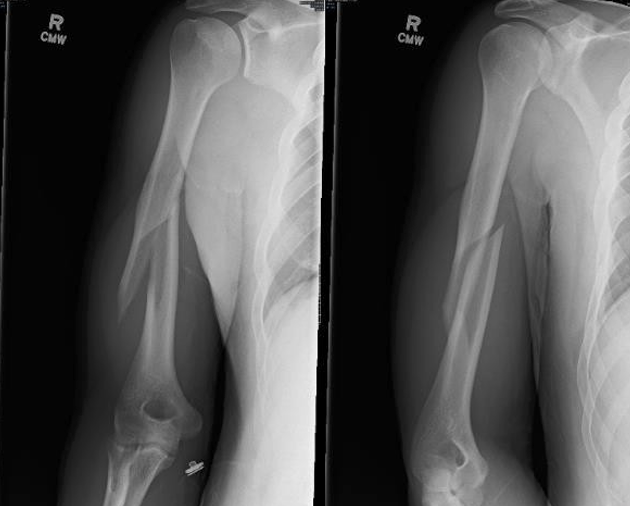

in the shown radiograph

1- what type of fracture

2- site of fracture

3- any dislocation

A

Comminuted fracture of proximal humeral metaphysis with shortening and dislocation of the shoulder joint